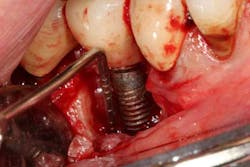

Fig.6